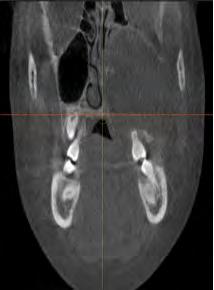

A 13-year-old male with no significant past medical history presented with a chief complaint of left maxillary facial swelling that had rapidly progressed over a six-month course. Social history was noncontributory. He denied any fevers, chills, recent weight loss or any other alarming symptoms. Exam was notable for pronounced upper left facial expansion extending along the malar process to the left eye, with left orbital proptosis and vertical dystopia. Doughy expansion was appreciated along the left malar process extraorally (Figure 1). Intraoral exam revealed extensive expansile doughy swelling at the upper left vestibule and hard palate with intact overlying gingiva. There were retained deciduous teeth in the posterior left maxilla, which were displaced with slight mobility (Figure 2). The patient had difficulty occluding due to pain. Vision was intact, with preserved extraocular movements. Cone beam CT scan showed an expansile cystic radiolucent lesion in the posterior left maxilla extending to the midline through the palatal and buccal bone, and encompassing the maxillary and ethmoid sinuses. The left orbital floor was intact (Figures 3-6).